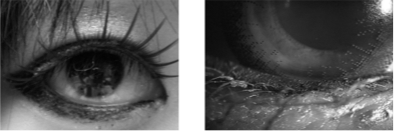

ところで、図1のように上下の睫毛の内側には、『マイボーム腺』という、目を乾燥から守るために大切な脂質がでる分泌腺があり、その出口が上まぶたに約25個、下まぶたに約 20 個あります。マイボーム腺からでる脂質は、目の表面の涙が乾かないように、重要な役割を果たしていて、いわば天然の美容液です。

最近流行のアイメイク法はまつ毛の内側にアイシャドウやアイラインを入れるので、このマイボーム腺の出口がメイクで塞がれ、涙が蒸発しやすくなり、ドライアイを起こすといわれます。メイクはまつ毛の外側にするようにして、マスカラもまつ毛の根元には塗らないように注意しましょう。

図1

図2 マイボーム腺の出口を塗りつぶすメイク

こんな、メイクをしてしまっていませんか?